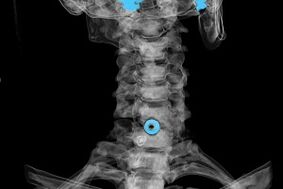

Diagnoze tiek noteikta, pamatojoties uz raksturīgiem simptomiem, kā arī izmantojot:

- rentgenstari. Metode ir neefektīva, īpaši pēdējos osteohondrozes attīstības posmos.

- Dzemdes kakla mugurkaula MRI (magnētiskās rezonanses attēlveidošana). Metode, kas ļauj redzēt kaulu struktūras, starpskriemeļu disku trūces, to lielumu un attīstības virzienu.

- Datortomogrāfija. Mazāk efektīvs risinājums nekā MRI, jo trūču esamību un lielumu ir grūti noteikt.